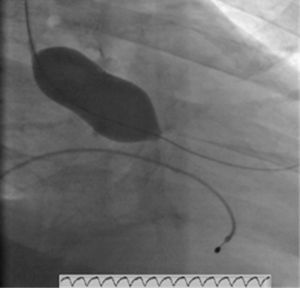

A coronariografia (Figura 2) revelou doença coronária de 2 vasos (lesão de 75% no segmento médio da descendente anterior e lesão de 90% na origem da descendente posterior). O estudo hemodinâmico determinou um gradiente transvalvular aórtico de 97mmHg.